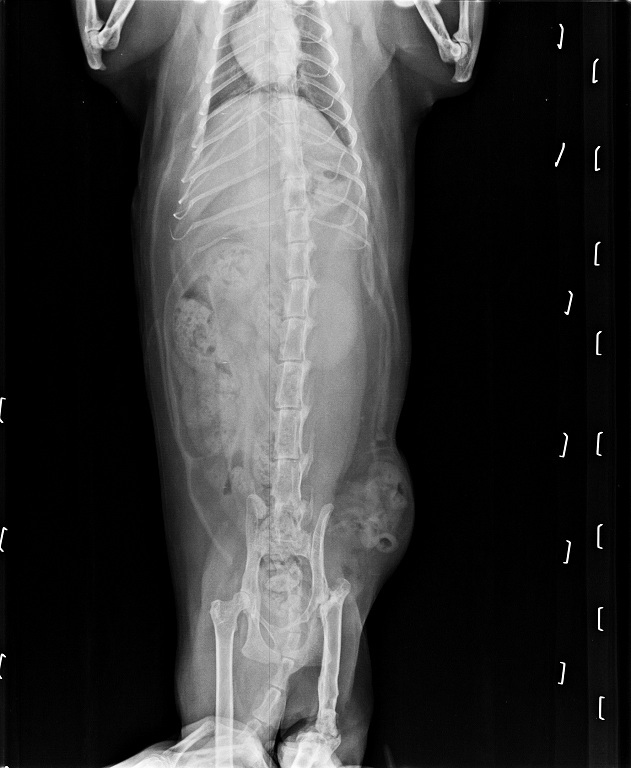

因此醫生幫乖妹做了超音波檢查和照X光,

而在看過X光照片之後,

醫生認為乖妹側腹部腫大的原因為疝氣,